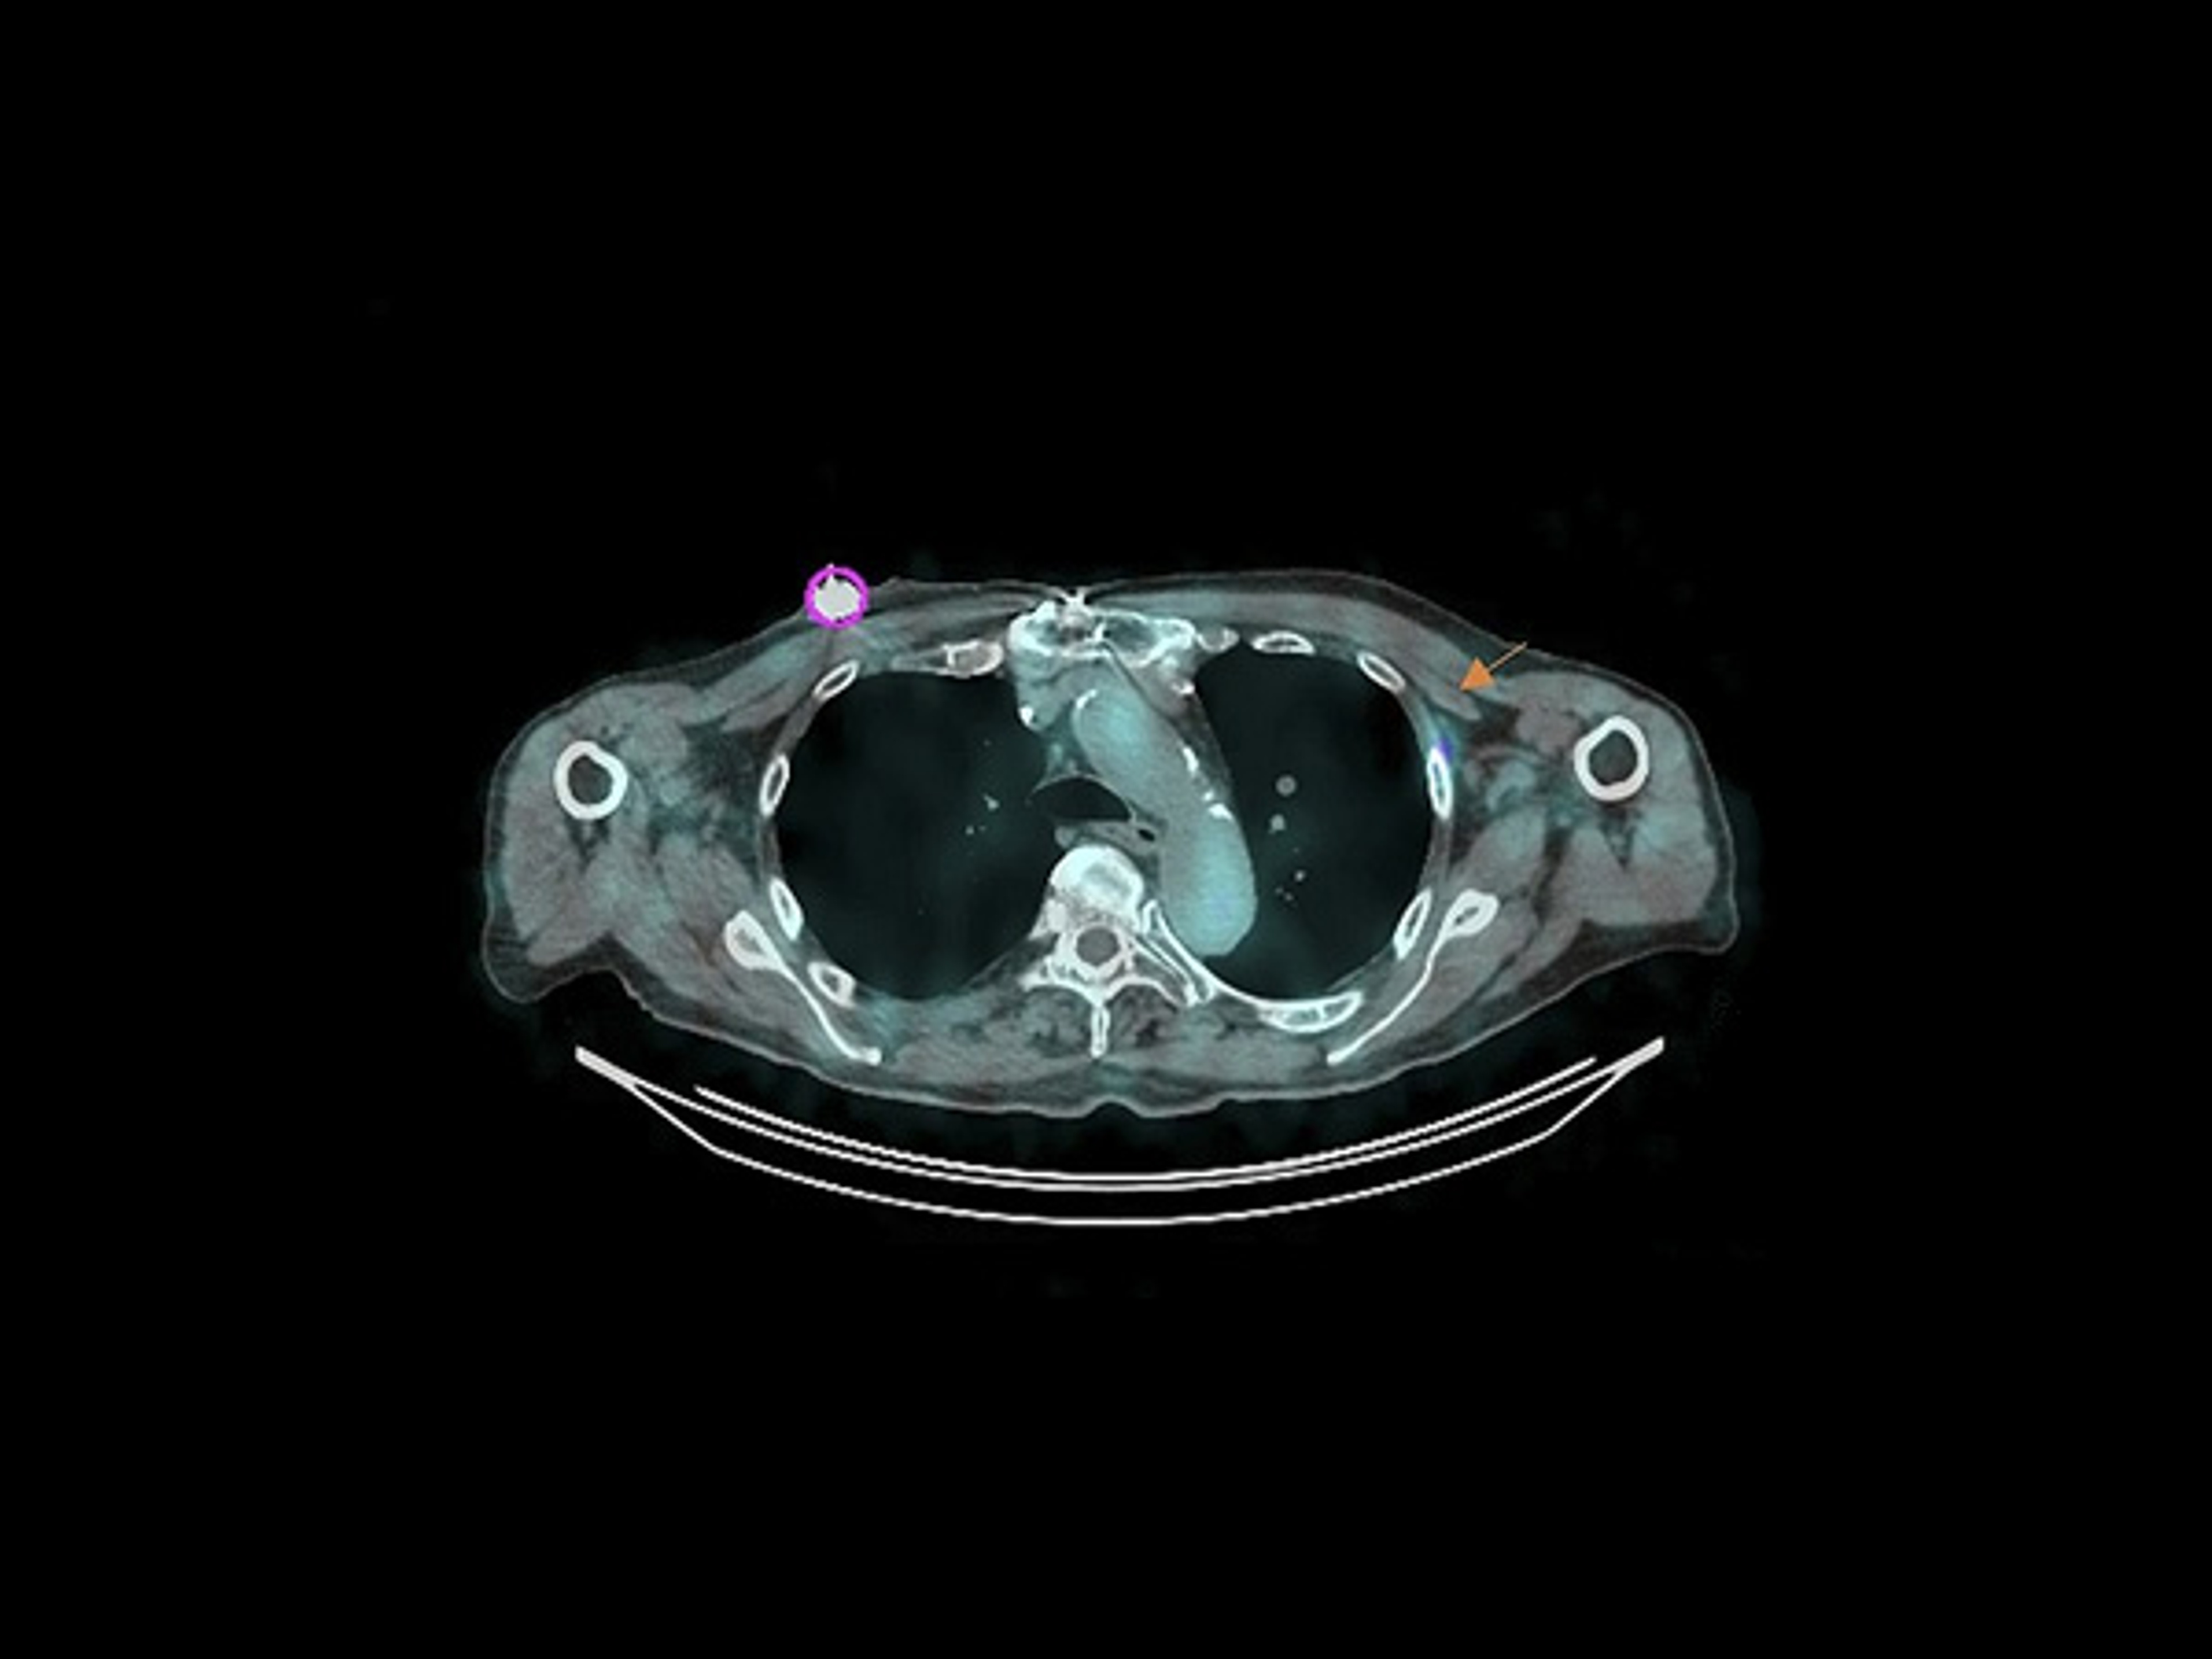

Feasibility and safety of [¹⁷⁷Lu]Lu-PSMA-617 administration via TIVAP confirmed